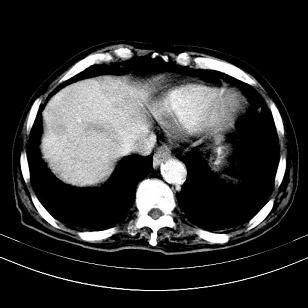

标题: CT19407:肝内还是肝外原发性肿瘤??

男,63岁,高血压病史40余年,

来源-右侧肾上腺。

考虑右侧肾上腺巨大占位;恶性?

肝内多发低密度找;转移瘤?

另:右肾结识,多发小囊肿。